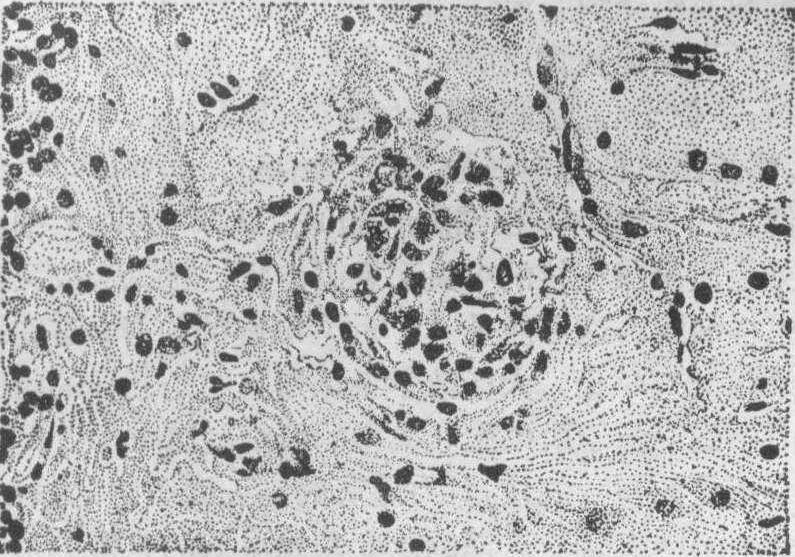

含铁小结 多见于高度淤血的巨脾中,为黄色或褐色的米粒大硬结,分散于红髓内。镜下见小结多为长条形或圆形,常在脾小梁附近。小结内有密集的纤维组织,苏木素伊红染色时常见三种不同颜色的物质: 在小结内有多数染成紫蓝色长短不一的纤维条,条间夹杂有灰绿色半透明杆状结晶样物质,外层有多量褐黄色的含铁血黄素颗粒。从前曾把这些杆条状物质当作真菌,误认是本病的病原体,其后证实它只是铁和钙盐沉积的胶原纤维。凡是能引起脾静脉淤血的病,如门脉性肝硬化、晚期血吸虫病等都能形成这种结节。可能是因为脾淤血时,有的小静脉因内压过大而发生小出血,出血后红细胞破坏,血红蛋白分解,形成含铁血黄素,同时出血机化,纤维组织增生,终于形成这样的小结。故此小结实为脾髓内陈旧小出血的遗迹。含铁小结还见于镰形红细胞性贫血,因镰形红细胞较易阻塞脾的小血管,引起局部组织缺血坏死,以后发生纤维化和钙化,同时坏死的红细胞分解形成铁质,在局部沉积而成。

图2 脾的含铁小结